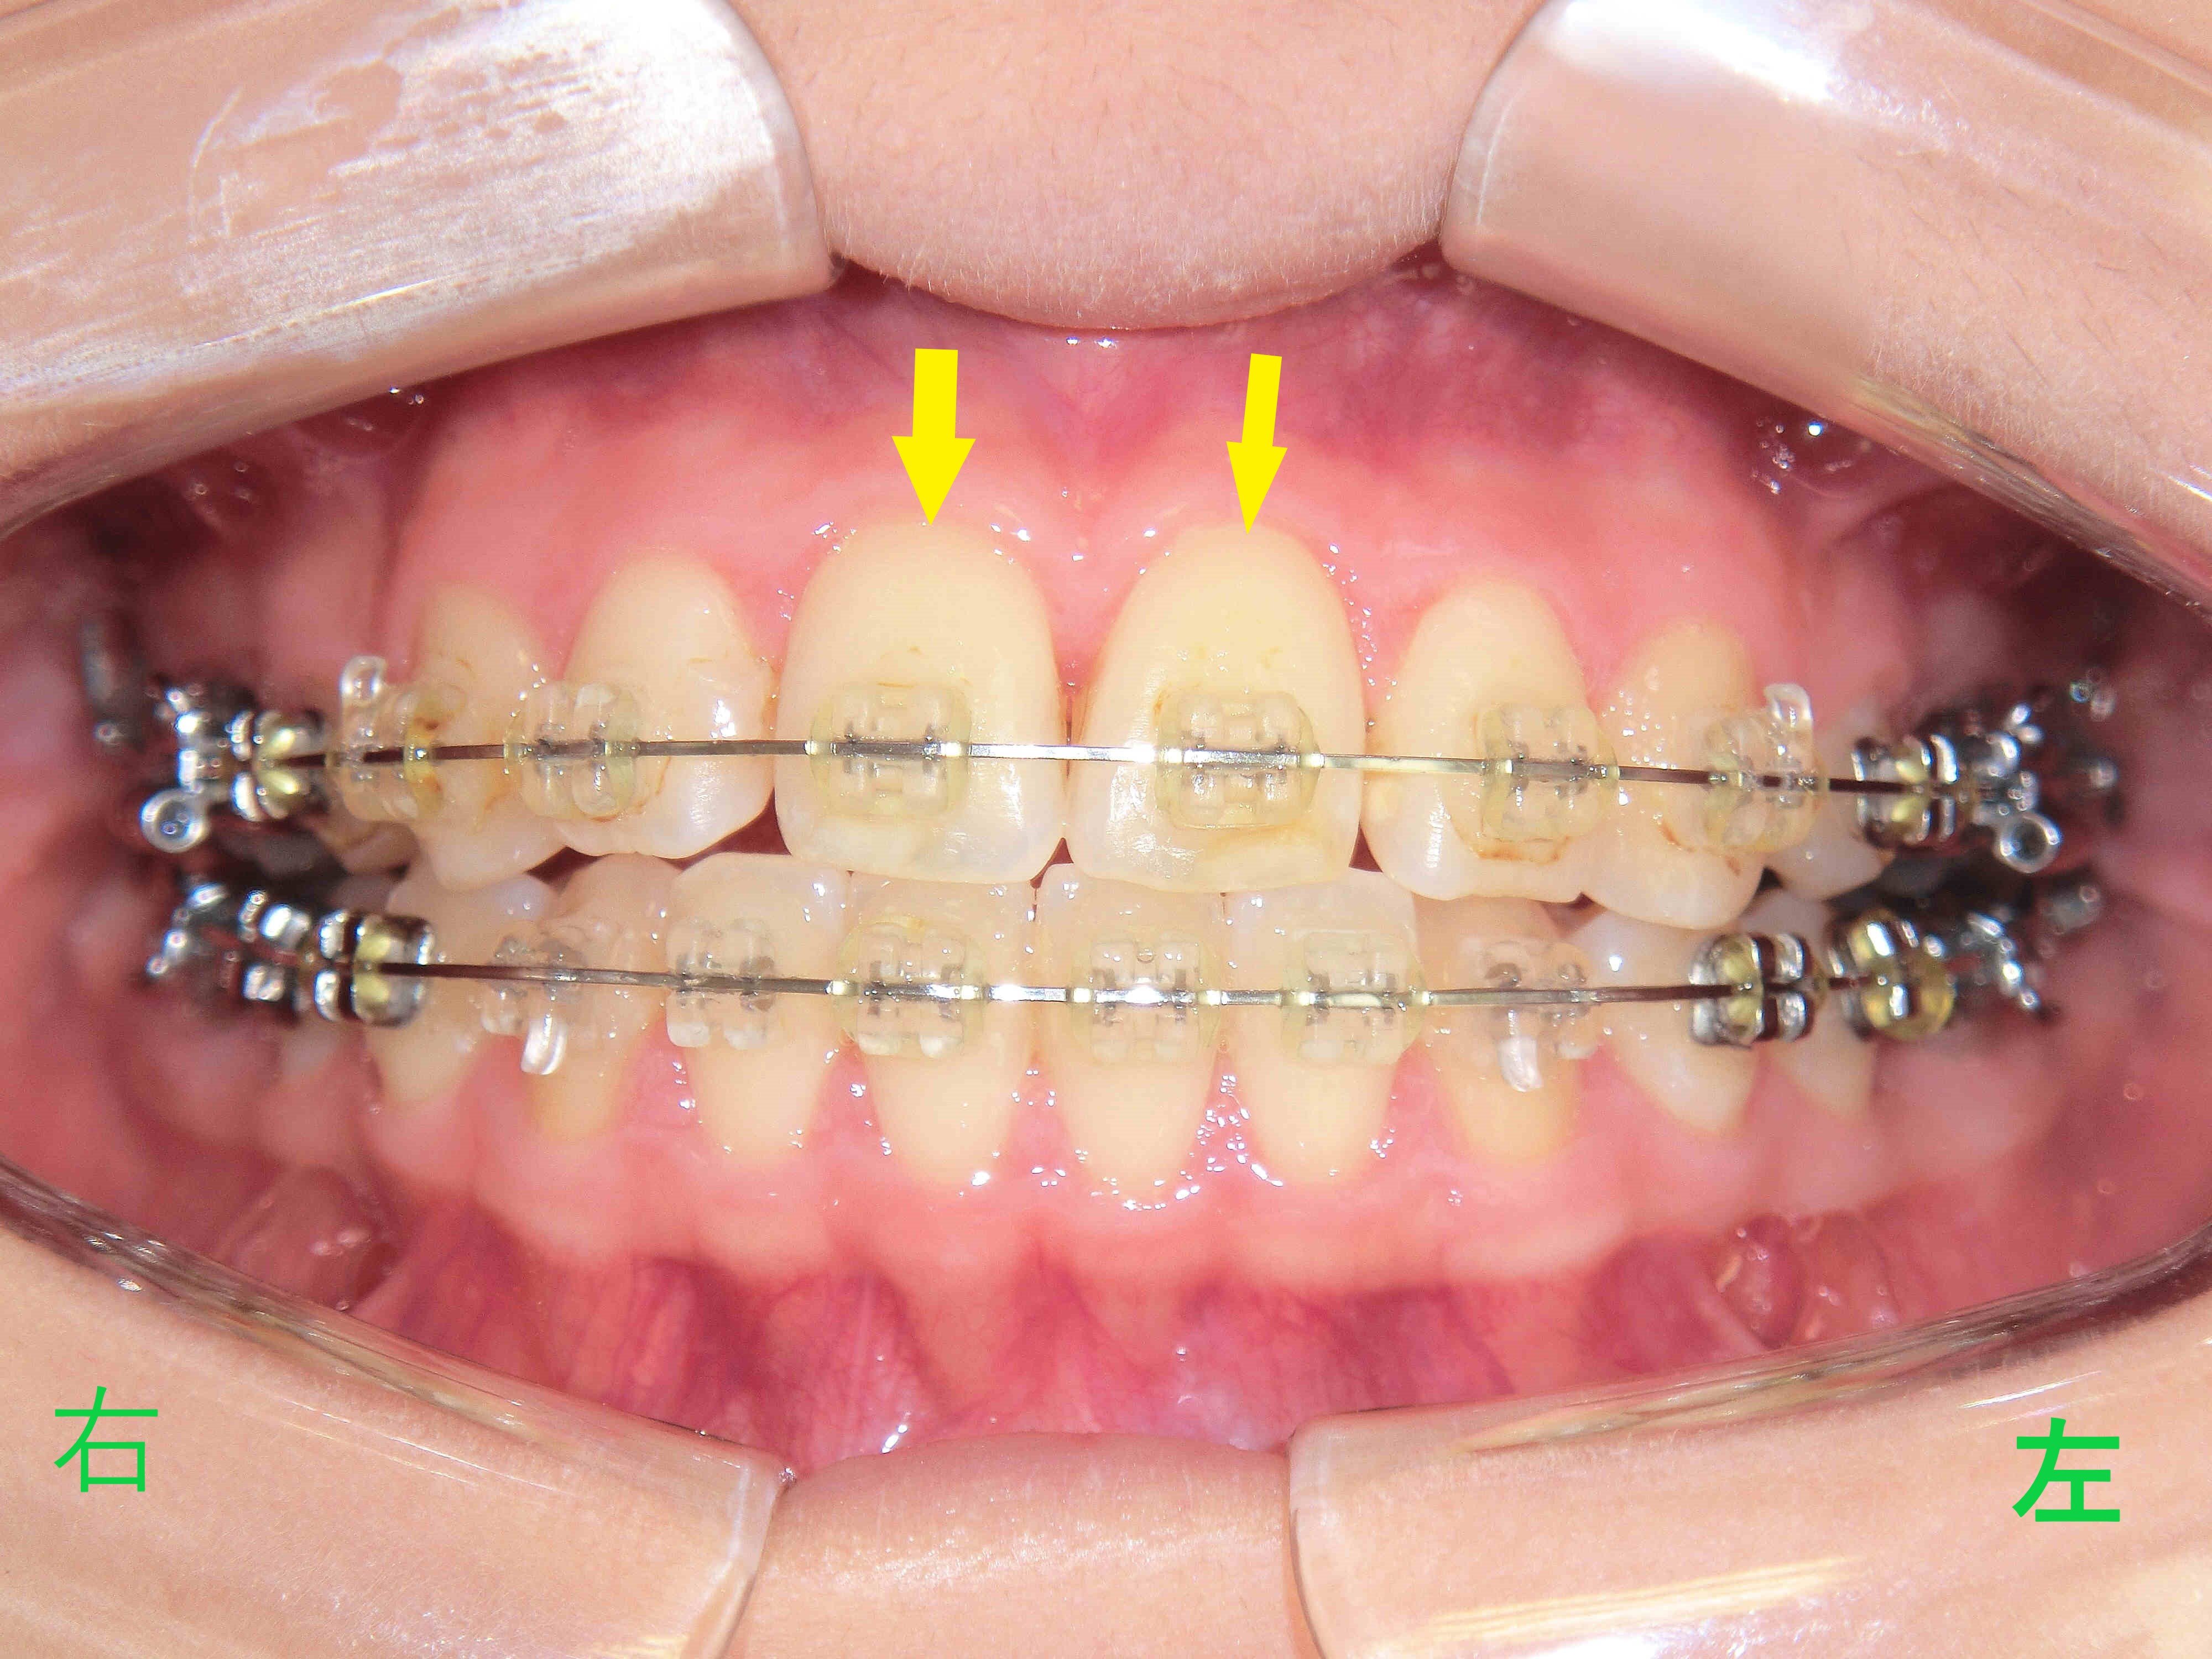

こちらは、矯正治療を開始して22か月後に撮影された口腔内写真です。

治療結果として口元や歯並びを患者様ご自身にご確認いただき、審美性および機能性に問題がないと判断されたため、矯正装置(ブラケットおよびワイヤー)の撤去を行いました。

上顎前歯(黄色矢印)が後方へ移動したことで、初診時に訴えがあった前突感(いわゆる出っ歯)は改善されました。

治療前と治療後の口腔内写真を比較すると、上顎前歯が後方へ移動し、下顎前歯との接触が確認できます。また、治療前はV字型であった歯列が、治療後はU字型に改善されています。